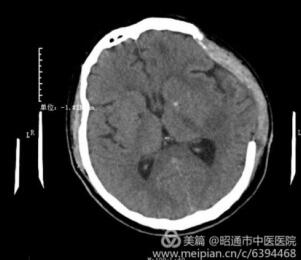

我院肿瘤科成功抢救重型颅脑损伤患儿

近日,一名儿童不慎从约4米高空跌落,家属及时送到我院,经检查,小孩头颅CT见少量硬膜...

高血压性脑出血患者在我院得到有效治疗

近日,我院肿瘤科主任李庭军与刚从华西医院神经外科进修归来的住院医师凌征龙,共同完成了...